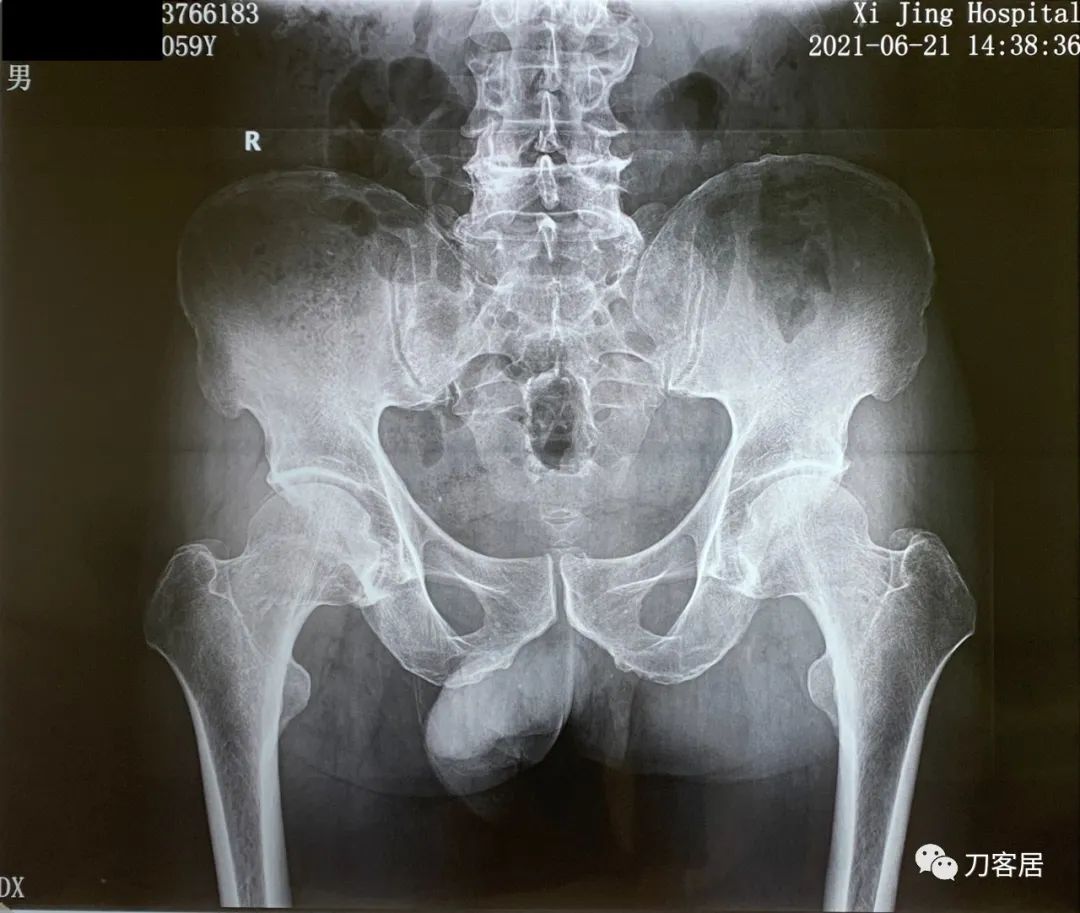

图2. 20210621西京医院骨盆平片